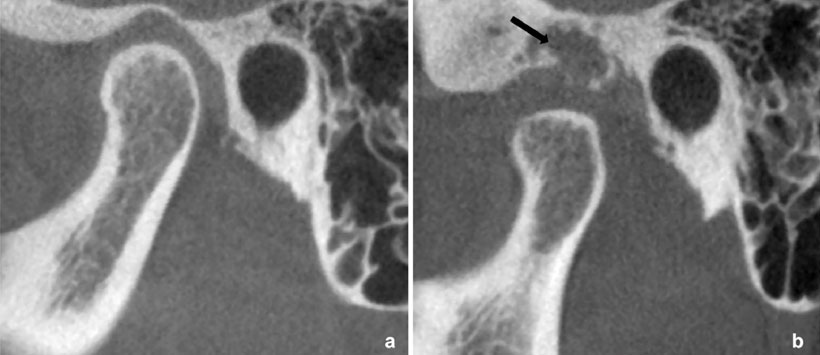

Caso 3: Mujer de 38 años con hinchazón pre-auricular izquierda desde hace 2 meses con sensibilidad y dolor a la palpación (Figura 6, 7 y 8).

Figura 7: Tomografía Computarizada (TC) en la que se aprecia múltiples masas hiperdensas irregulares y de diversas formas observados en la vista axial (a) y coronal (b).

Figura 8: Tomografía Computarizada (TC) en la que se aprecia aumento del espacio articular del lado afectado con erosión severa de la cavidad glenoidea (flecha negra).